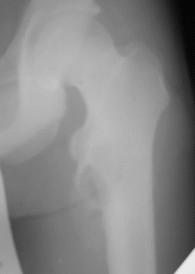

Обратился парень 15ти лет с жалобами на боли в левом коленном суставе. При обследовании обнаружена опухоль в в/з левой бедренной кости.

Проведено КТ заключение( остеохондрома) Подскажите пожалуйста, стоит ли сделать биопсию перед операцией .Кокой операционный доступ и технику операции Вы посоветуете.